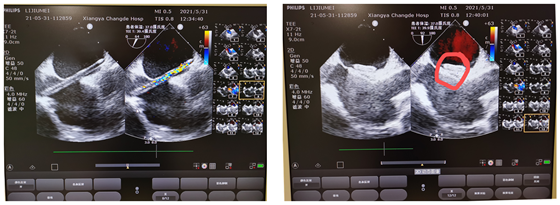

58岁的李阿姨近10年来反复出现头痛、头晕等不适,曾就诊于多家医院,完善各项检查均无异常,未查出病因,仅服用止痛药物,治疗效果差,病情反复发作。一个月前,李阿姨来到湘雅常德医院,并在我院神经内科知名专家门诊完善相关检查后,其头痛原因考虑与卵圆孔未闭有关,后求诊于心胸外科主任黄日茂副教授。黄日茂副教授为患者查体后认为:心脏右心声学造影在Vasalva动作后可见右心房大量气泡经卵圆孔处流入左心房,考虑卵圆孔未闭,建议封堵手术治疗。

入院后完善相关检查,排除其他可能只“头痛、头晕”的疾病,黄副教授团队在进行手术前讨论一致认为,李阿姨有明确封堵手术适应症,无手术禁忌症。在告知家属并签署手术同意书后于5月31日行无射线零辐射单纯超声引导下卵圆孔未闭封堵术。